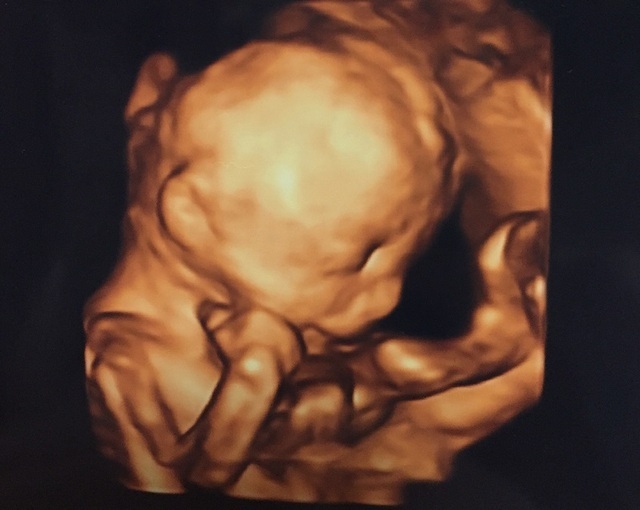

21週0日(21w0d・男の子)|ゆいぷる さん(31歳)

エコー写真撮影時のエピソード:

こんなにはっきりした赤ちゃんのエコー写真ある⁉️と夫婦でびっくりしました。 どっかの銅像でありそうだよね!と笑いながら話しました。

この顔、旦那さんにそっくりで、俺似だ!とすごくうれしそうに話してたのを思い出しました。